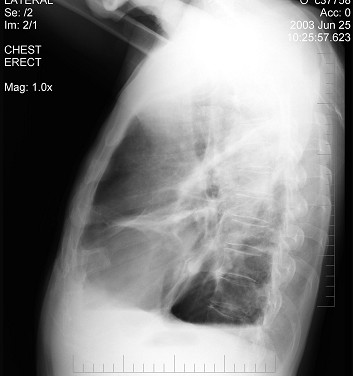

[单选题]男,62岁,常感胸闷、气逼,X线检查如图,最可能的诊断是()A.右侧肺大泡B.右侧气胸C.右侧肺脓肿D.右侧胸膜肥厚E.右侧肺气肿

[单选题]男性患者,62岁,常感胸闷、气逼,X线检查如图,最可能的诊断是()A .右侧肺大疱B .右侧气胸C .右侧肺脓肿D .右侧胸膜肥厚E .气胸